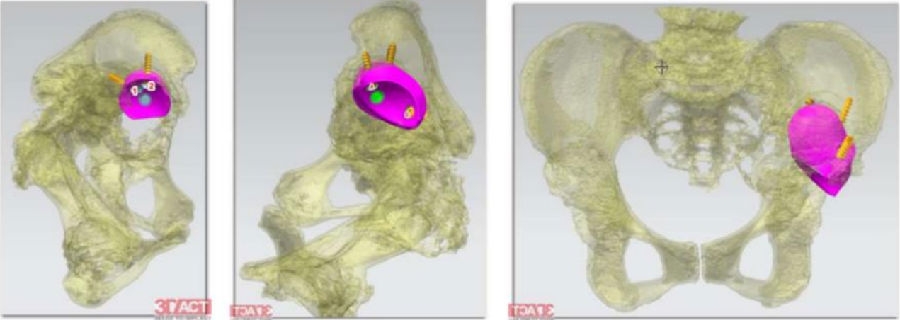

患者女性,7岁,右侧全髋关节置换术后16年,髋臼侧假体松动移位,合并严重的骨缺损和右下肢短缩(图5),诊断为“右髋关节置换术后假体无菌性松动”。手术前通过对CT影像进行降噪、分割、骨缺损范围识别后,对骨缺损修复和髋臼假体位置进行3D规划,手术由田华主任和李锋教授共同完成(图6)。

术中,VTS导航系统不仅可以追踪髋臼磨锉、假体位置和前倾角/外展角等关键角度信息,还可以对补块位置进行示踪(图7),将补块和假体安放的位置和角度精确到1mm和1°,从而最大程度地避免了人工操作的误差和对重要生理结构的副损伤,大大提高了骨缺损修复的精准性和手术操作的安全性。术后患者恢复良好,影像学显示补块及假体位置满意(图8),术后第二天即可下地活动。

图7 翻修手术规划过程中骨缺损修复补块的安装及螺钉的可视化追踪